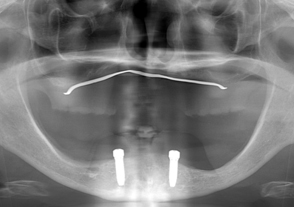

- 治療後のレントゲン